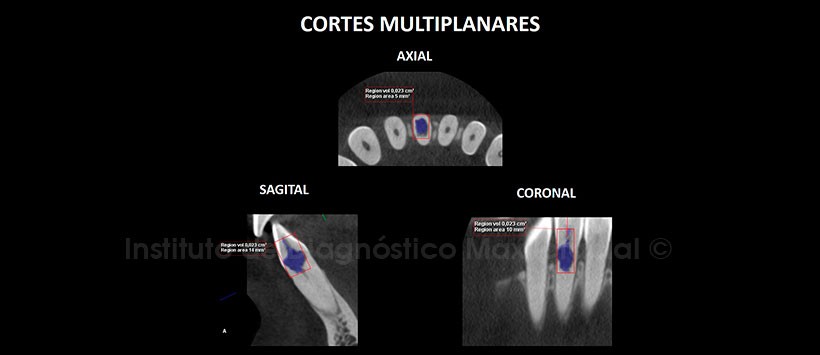

A la evaluación de la radiografía Panorámica (Figura 1) se apreció una imagen radiolúcida de contorno irregular en el tercio cervical de la pieza 41 además de falta de definición del conducto radicular en el tercio medio y apical. A la evaluación de la tomografía computarizada Cone beam mediante cortes axiales, coronales, sagitales (Figuras 2 y 3) y transaxiales (Figura 4), se encontró la presencia de una imagen hipodensa de contorno irregular en el tercio cervical en relación al conducto radicular, que muestra una marcada extensión ocasionando la erosión de la superficie radicular en la zona cérvico distal condicionando comunicación con el espacio periodontal. Signos tomográficos de proceso de reabsorción radicular interna.

Se evidenció, así también, obliteración del conducto radicular en el tercio medio y apical. Probable relación a secuela post traumática.

Los estudios por tomografía Cone beam permiten detectar claramente la conformación de la zona afectada, permitiendo determinar la afectación de estructuras, así como incluso las dimensiones en volumen de la zona de reabsorción.